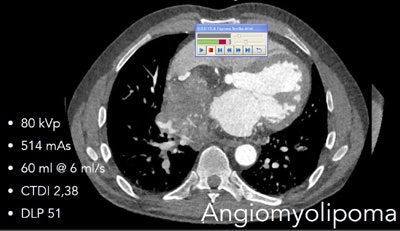

Angiomyolipoma contains areas of calcium and fat, imagined at DSCT in high-pitch scan mode, in image acquired at 80 kVp. Dose was 0.61 mSv. Coronary arteries and tumor extent are clearly visible, as are areas of fat and calcium within the tumor, which caused the patient no disability for a decade.